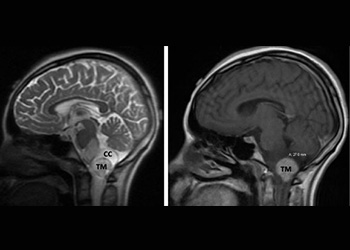

Figure 3. Immediate post-op CT (left) and two-year follow-up MRI (right).

Following, the intramedullary brainstem tumor was successfully resected via suboccipital craniotomy and upper cervical laminectomy. The patient did well after surgery.

Five years following surgery, the patient is fully recovered, and is a thriving high school senior.